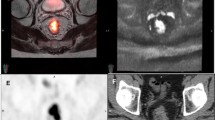

In the evaluation of metastatic disease, PET/MRI is particularly valuable for hepatic staging both given that the liver is a common site for metastatic disease and that MRI is the reference standard in liver imaging. Hepatobiliary phase (HBP) MRI of the liver is the preferred imaging modality to identify colon cancer liver metastasis [4]. Other investigators have shown added value of whole-body-integrated PET/MRI over contrast-enhanced CT alone in the detection and characterization of metastatic lesions [16, 17]. Combining HBP MRI in the setting of a rectal PET/MRI is feasible although care has to be taken to keep the total scan length to a reasonable time (Figs. 4, 5). Results of one retrospective study suggest PET/MRI may aid in the selection of more appropriate treatment strategies for colorectal cancer patients, with the treatment strategy changed in 21% of patients after PET/MRI added information to the CECT findings [18].

A 52-year-old man with a newly diagnosed rectal adenocarcinoma. A whole-body PET/MRI with dedicated rectal and liver bed positions was performed (a). In the rectal bed position, a 5-mm right perirectal node is seen which demonstrates hypermetabolism consistent with nodal metastatic disease (b circle, d and f black arrow). In the liver, a 6-mm caudate lobe lesion was visualized on hepatobiliary phase imaging (c), which demonstrated hypermetabolism (e and g, black circle) consistent with hepatic metastatic disease